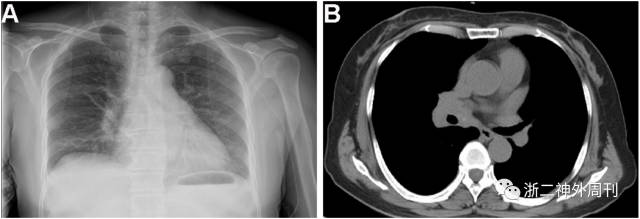

(3) 术前常规胸部X片(图2-A)提示右侧肺门增大影。

(4) 胸部高分辨率CT(图2-B)右肺中叶肿块影,右肺门肿大淋巴结

图2. 胸部X片提示右侧肺门增大影(A);胸部高分辨CT检查提示:右肺中叶肿块影与淋巴结肿大(B)。